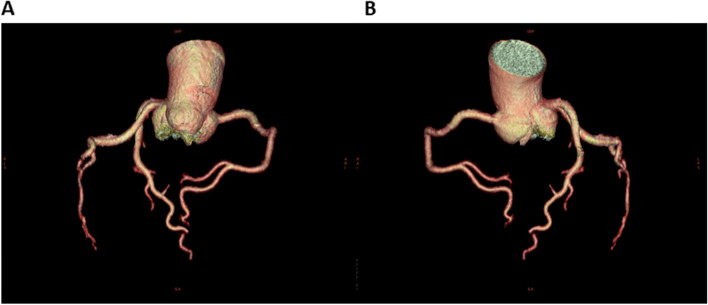

Based on her clinical course and imaging findings, she was diagnosed with reversible cerebral vasoconstriction syndrome (RCVS) with cardiac involvement. We administered 5 mg of the calcium channel blocker amlodipine besylate, 25 mg of nitroglycerin, and 500 mg of the antiepileptic drug levetiracetam. The hyperintense regions on FLAIR images completely disappeared 23 days after onset of first headache. She showed no exacerbation of heart failure, and the ECG (Fig. 3B) and UCG (Fig. 4B) findings were found to be normal eight days after onset of first headache. To avoid the risk of vascular spasm by iodinated contrast medium, we did not perform cardiac catheterization or coronary computed tomography (CT)-angiography until her RCVS was fully controlled. Since no recurrence of symptoms was observed after the treatment, we performed coronary CT-angiography seven months after the onset, which showed no significant vasoconstriction in any coronary artery (Fig. 5A, B).

A notable feature of this case was that reversible cardiac involvement occurred concomitantly with RCVS. Despite the absence of chest symptoms, an increase in serum BNP levels, ST-T changes on ECG, and decreased EF and FS on UCG were seen and improved three days after therapy was started. This implies that there is cardiac involvement caused by Takotsubo cardiomyopathy or abnormalities in coronary arteries. So far, it has been reported that in a retrospective study 68 cases, from which 18 had patients had undergone UCGs around the period of active RCVS. Among them, three female patients who had no coronary artery disease or heart failure presented with wall motion abnormalities on UCG [ref. 9]. This report concluded that cardiac ventricular abnormalities may be a part of the RCVS spectrum. In another report, a middle-aged female patient with RCVS showed coronary artery spasm. The patient, with repetitive chest pain and transient wall-motion abnormalities on UCG, had experienced a thunderclap headache, and diffuse cerebral vasoconstriction was revealed on cerebral angiograms [ref. 10]; in this case, RCVS had developed after repeated coronary artery spasm. However, our case presented both cerebral and cardiac lesions almost coexisted. We did not perform the coronary angiography to avoid the adverse effect such as vasoconstriction by the contrast medium; however, coronary vasospasm may have occurred by the mechanism like that of cerebral vasospasm. Whilst, based on the UCG findings and ECG changes that cannot be explained by the distribution of coronary arteries, catecholamine cardiomyopathy such as reverse Takotsubo cardiomyopathy may have occurred by severe pain from thunderclap headache [ref. 11].